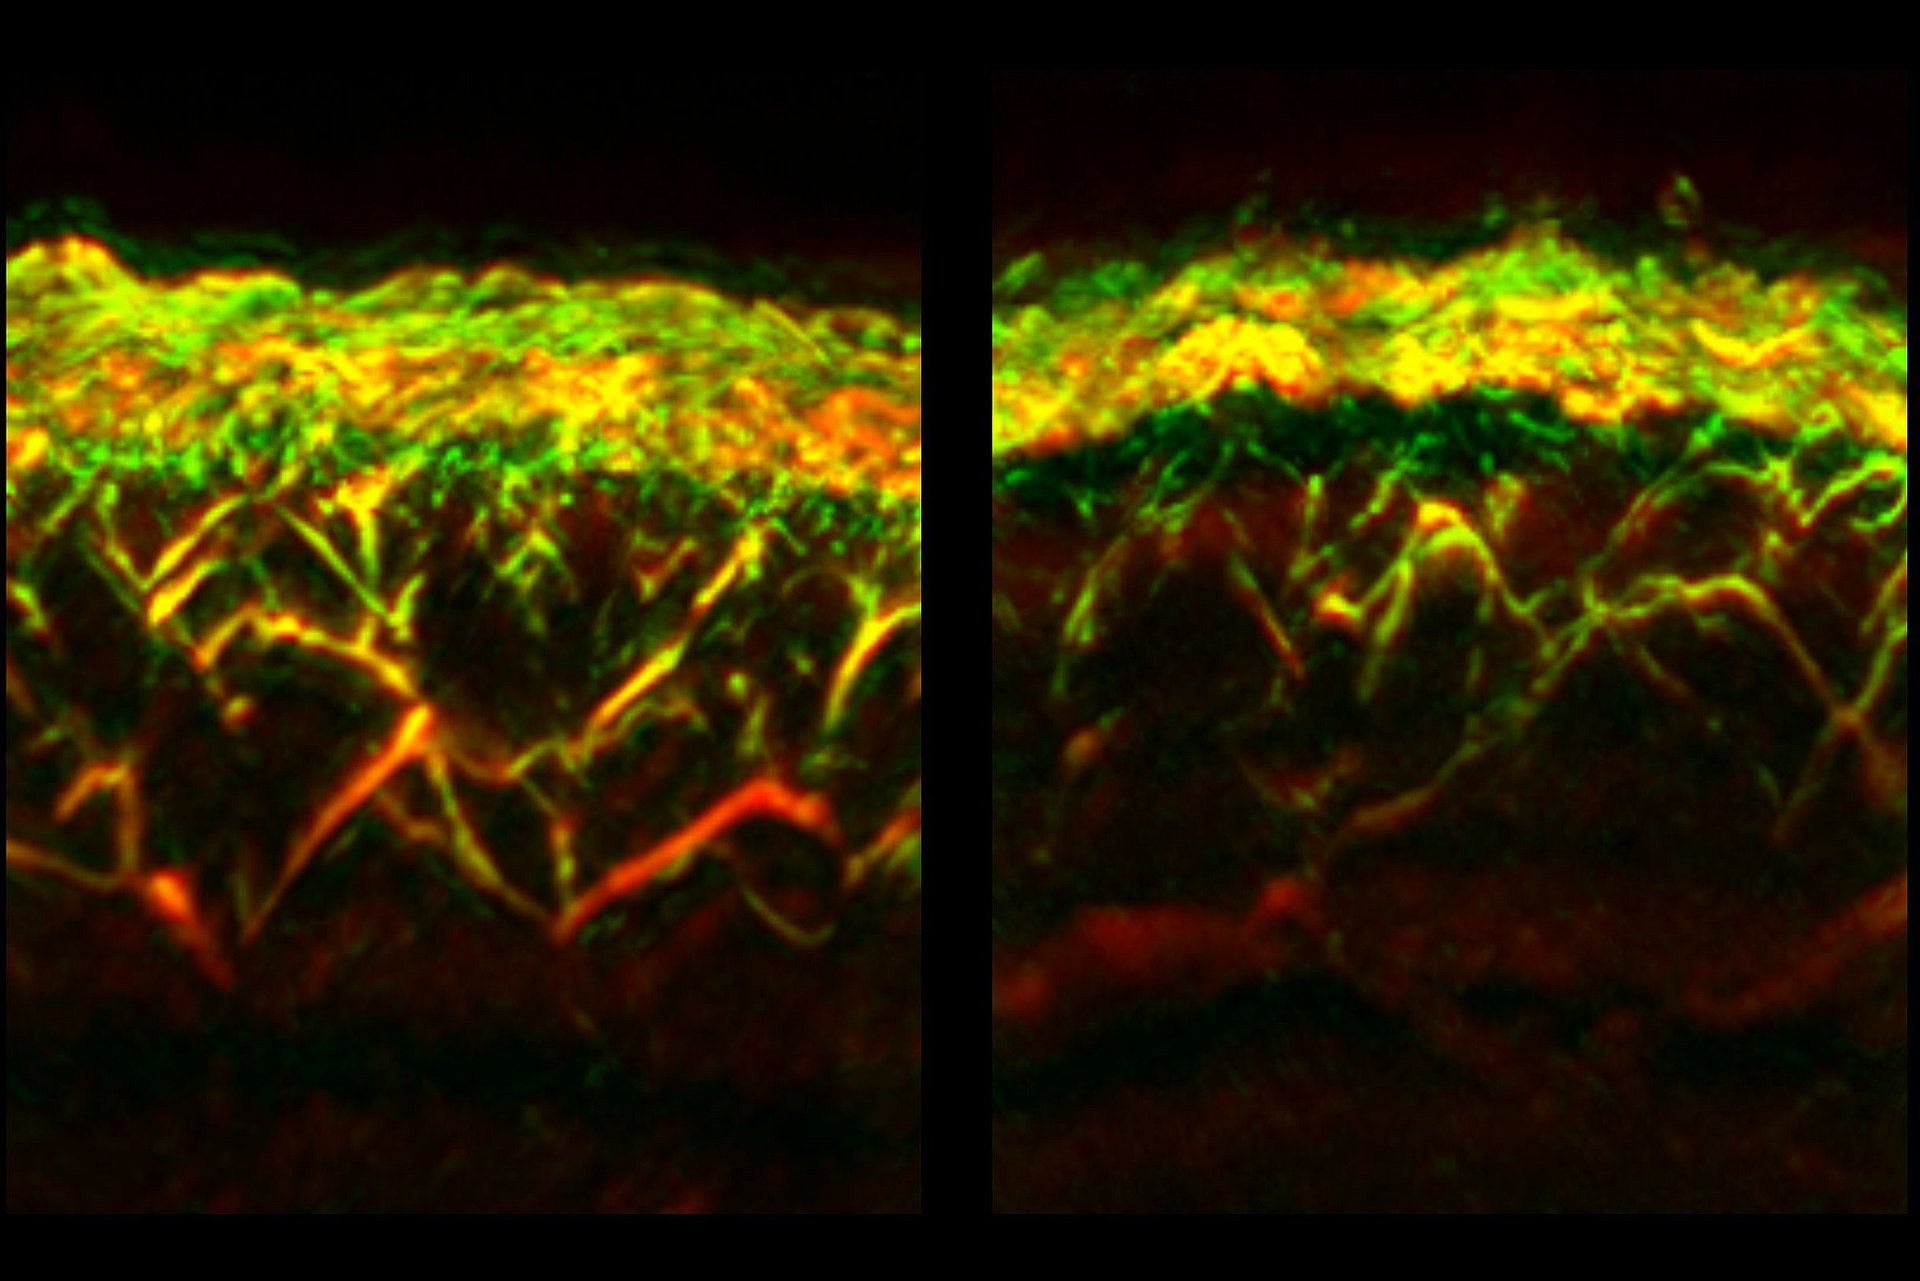

With a single RSOM measurement, data on different depths of the skin can be obtained simultaneously. This enabled the researchers to determine for the first time that diabetes affects vessels at different skin layers differently: For example, while the number of vessels and branches in the so-called dermal layer were reduced in diabetics, they were increased closer to the surface of the skin, in the so-called epidermal layer.